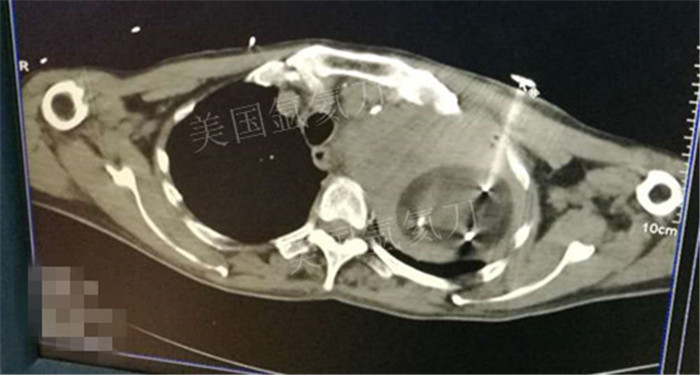

下一篇:氩氦冷冻治疗最大径8.2肿瘤,冰球最大径7.9